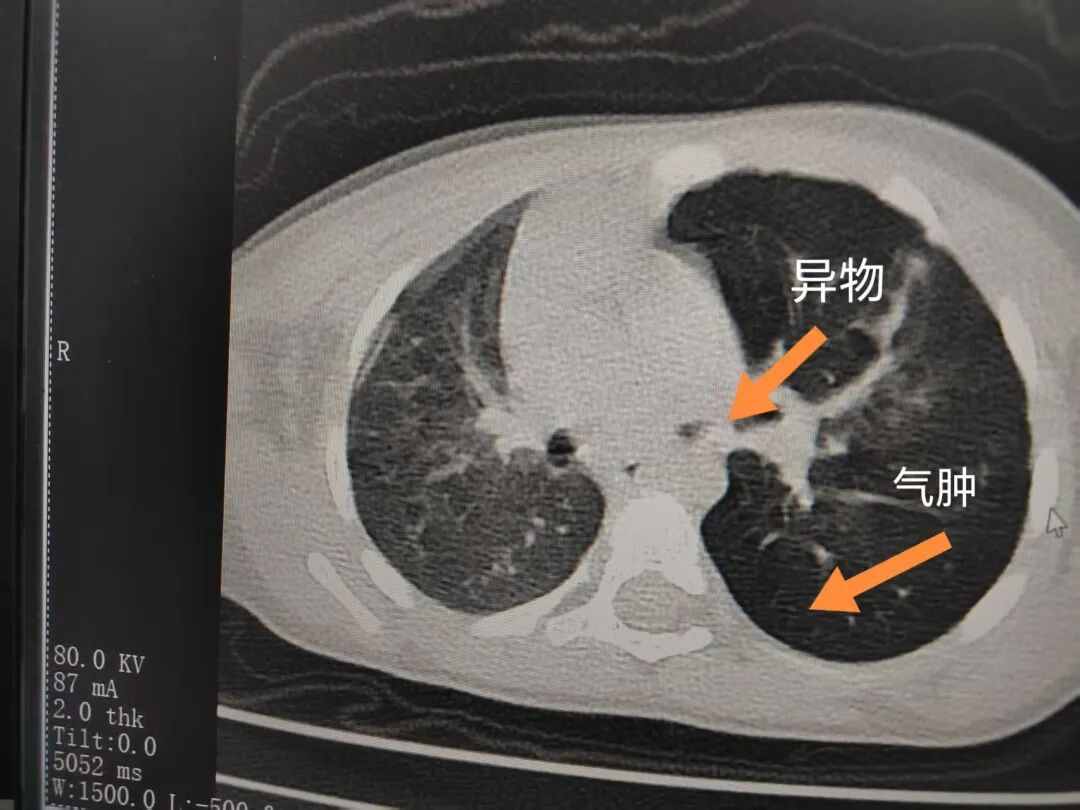

三天后(11月13日),趙寶出現(xiàn)高熱、咳喘加重,家長著急了,再次帶他來到醫(yī)院。CT檢查顯示左肺過度充氣,左肺上下葉支氣管主干見不規(guī)則高密度影,左肺上葉可見大片狀密度增高影,縱隔窗實變,提示為“左側(cè)支氣管內(nèi)異物并繼發(fā)性改變,左肺上葉舌段肺膨脹不全”。

市二院小兒呼吸內(nèi)科副主任楊亞娟介紹,異物誤入氣道可能導致氣道阻塞,嚴重時可引發(fā)窒息,甚至危及生命。若異物進入支氣管,造成不完全堵塞,可引起阻塞性肺氣腫;如完全堵塞支氣管,則可能導致肺組織萎縮,形成肺不張。此外,若異物存留時間較長,或為植物性異物,容易合并細菌感染,產(chǎn)生膿性分泌物,進而發(fā)展為肺炎。她強調(diào),盡早診斷并取出異物,是減少并發(fā)癥、降低病死率的關(guān)鍵。